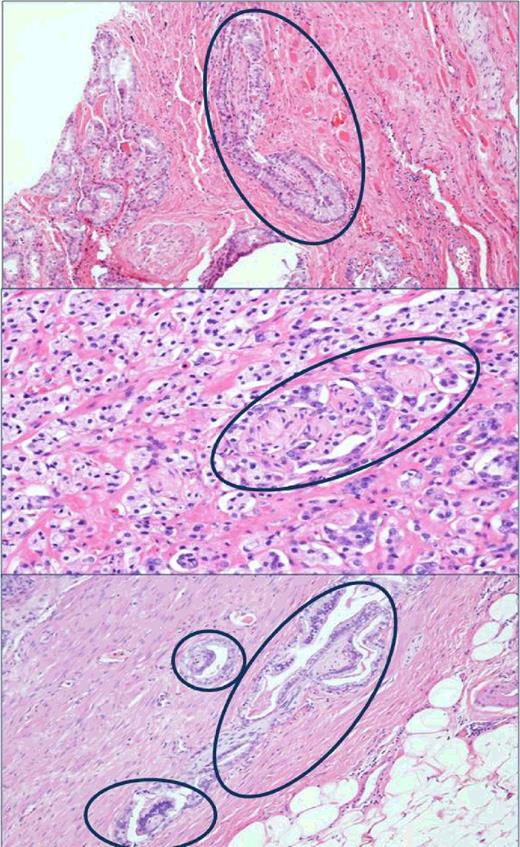

Men in the Swedish cohort were, on average, older at the time of diagnosis than those in the HPFS (mean age 73.0 years vs. 66.0 years, respectively). Tumors in the Swedish cohort tended to be of lower grade, although the proportion of men with high grade (Gleason ≥8) tumors was similar (19% vs. 25% in the Swedish cohort and HPFS, respectively), the proportion of men with Gleason 7 tumors was significantly higher in the HPFS (58% vs. 34%). Most tumors (59%) in the Swedish cohort were staged as T1b (defined as >5% of resected tissue involved with cancer or Gleason grade ≥7). In the HPFS, 72% of men had localized tumors at prostatectomy (≤pT2). Figure 1 shows H&E slides with PNI adjacent to prostate cancer.

Hematoxylin and eosin–stained tissue slides showing the presence of PNI adjacent to prostate cancer, HPFS.

One dedicated genitourinary pathologist (M. Fiorentino) undertook a systematic histopathologic review of all available H&E slides for each case, blinded to patient outcome, for the presence or absence of PNI, Gleason grade, pathologic tumor stage (1997 American Joint Committee on Cancer TNM Classification), high-grade prostatic intraepithelial neoplasia (hgPIN), acute and chronic inflammation, and patterns of atrophy (simple atrophy, simple atrophy cyst formation, partial atrophy, and post-atrophic hyperplasia). TURP specimens were also assessed for tumor volume (as measured by the percentage of the specimen involved with cancer). The presence or absence of PNI was assessed in each available tumor slide. PNI was defined as the presence of complete circumferential encirclement of nerve structures by malignant glands. Cases with noncircumferential PNI or a single focus of PNI among multiple tumor slides were deemed PNI-negative.